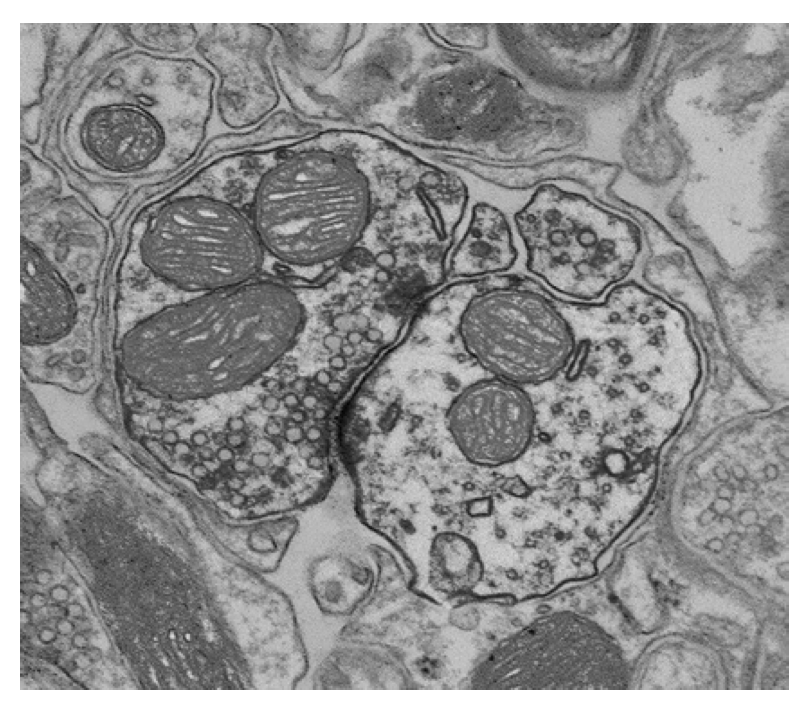

На микрофотографии представлен синапс